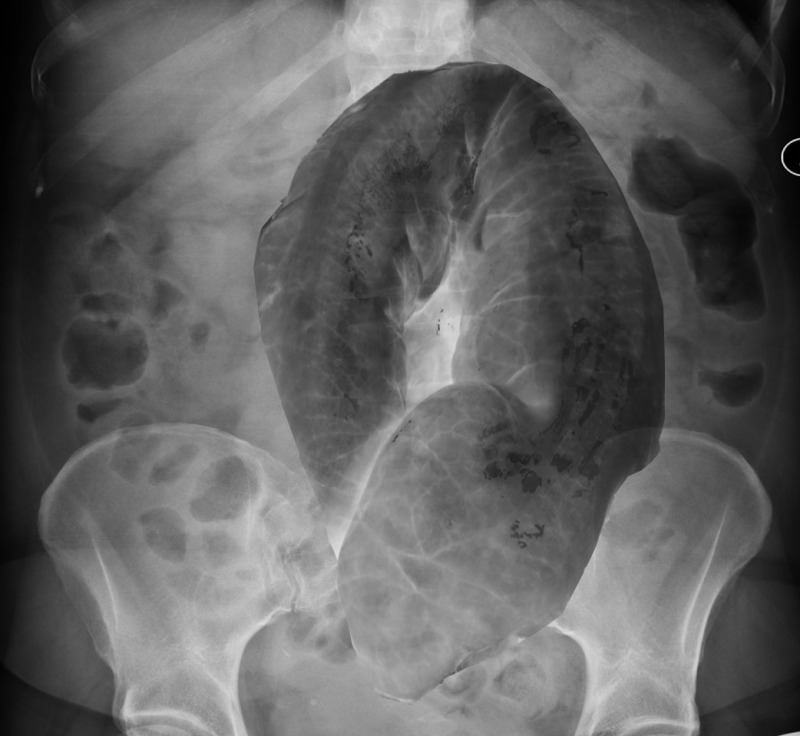

Contributors: Travis Barlock MD, Jeffrey Olson MS4 Feel free to use the cases below for your own practice. All of the scenarios are completely made up and designed to hit several teaching points. Case 1 25 M, presents to the ED with chest pain. Stabbing, started a few hours ago, substernal. Thinks it is GERD. After 2-3 minutes, pain worsens and radiates to the back. VS: BP 125/50 (Right arm 190/110). HR 120. RR of 18. Sat 98% on RA. Additional VS: Temp of 37.2, height of 6'5", BMI of 18. PMH: None, doesn't see a doctor. Meds: None FH: Weird heart thing (Mitral Valve Prolapse), weird lung thing (spontaneous pneumothorax), tall family members with long fingers and toes Physical Exam: Cards: Diastolic decrescendo at the RUSB, diminished S2. UE pulses are asymmetric, LE pulses are asymmetric, carotid pulses are asymmetric, BP is asymmetric MSK: Knees, elbows, and wrists are hypermobile. Imaging: CXR #1 normal, #2 widened mediastinum (no read yet but shows widened mediastinum), POCUS shows small effusion CTA/MRA doesn't come back until after the case. ECG: Sinus Tach Labs: NT-proBNP 500 pg/mL D-Dimer: 7000 ng/L CBC: Hemoglobin: 13.5 g/dL, WBC: 20,000/µL, Platelets: 250,000/µL Chem 7: Na 138, K, 5.7, Cl 102, Bicarb 17, BUN 45, Creatinine: 3.5 mg/dL, Glucose: 180 LFTs: Albumin 2.4, Total protein 5.5, ALP: 140, AST: 3500, ALT: 2800, TBili: 3.2, DirectBili: 2.4, Ca: 7.8 LDH: 2200 PT: 20.5, INR: 2.2, Fibrinogen: 170 5th gen High-Sensitivity Troponin: <3 Lactate: 7 mmol/L VBG: pH 7.22, paCO2 28, bicarb 15 Notes: Can have patient crash somewhere in middle and show 2nd xray Case 2: A 67-year-old female is brought to the ED by her daughter due to progressive weakness, confusion, and fatigue that have worsened over the past week. Unable to get out of bed and has become increasingly lethargic. Also having some nausea, constipation. The daughter denies any preceding illness, recent trauma, or travel. Does not know her meds but will head home to get them after talking with you. VS: BP 88/55 mmHg, HR 110, RR 20, O2 Sat 98% on room air. Additional VS: Temp 36.8°C. PMH: Hypertension, osteoarthritis, and depression. Physical exam: General: Thin, somnolent but arousable. HENT: Dry mucous membranes Neuro: Confused, A&Ox1 (self), hyporeflexia Labs (Includes many that would not return in the ED in case you want to take this case forward to the floor) CBC: WBC 9,500, Hb 16.5, Hct: 50%, Platelets 220,000 Chem7: Na 129, K 2.1, Cl 95, HCO3 34, Creatinine 1.6, BUN 40, Glucose 115 LFTs: normal Magnesium: 1.1 Calcium: 10.8 mg/dL (corrects to 12.8) iCal: 3.2 Phosphate: 2.3 mg/dL Albumin: 2 BUN:Cr ratio: 25 VBG: pH: 7.49, PaCO2 45, HCO3: 34 Lactate: 2.8 Serum Osmolality: 276 mOsm/kg (Osmolal gap of 2) Urine Osmolality: 550 mOsm/kg Urine Sodium (UNa): 10 mEq/L (low). Urine Potassium (UK): 25 mEq/L (elevated). Urine Chloride (UCl): 12 mEq/L (low). Urine Magnesium (UMg): 20 (Elevated). Urine Calcium (UCa): 50 in 24 hrs (Low) 100 cc of urine with foley FeNa Plasma renin activity: 15 mg/mL/hr (elevated), Aldosterone: 25 ng/dL (Elevated), ADH: Elevated, Diuretic screen: Positive for thiazides PTH: 8 (low), HsTrop: 32, Cortisol and ACTH: Normal. EKG: Hypokalemia features CXR: Normal Renal US: shows stones Improves with fluids Note: Can have daughter return with med list at some point including HCTZ, ibuprofen, and sertraline Case 3: Patient Presentation EMS Report: A 27-year-old male involved in a high-speed motorcycle collision is brought to the emergency department by EMS. The patient was found unconscious at the scene with evidence of severe thoracic and extremity trauma. He was intubated en route for airway protection due to altered mental status (GCS 7). VS: HR 130, BP 90/60, RR: bagging at 12 bpm, satting 88% on 100% FiO2 Primary Survey Airway: Endotracheal tube in place. Breathing: Decreased breath sounds on the left side with visible chest asymmetry and paradoxical chest wall movement. Circulation: Mottled extremities noted, with significant deformity of the right thigh. Pulses are diminished in the right leg Disability: GCS remains 7 (E1 V2 M4). Pupils equal and reactive. Exposure: Full-body examination reveals an open fracture of the right femur, multiple abrasions, and bruising over the chest wall. Vent alarms Peak Inspiratory Pressure (PIP) 40 cm H₂O (elevated) Plateau Pressure (Pplat) 35 cm H₂O (elevated) EtCO₂ (End-Tidal CO₂) 55 mmHg High-Pressure Alarm Triggering frequently Glucose 120 CBC: Hgb 8.9, Hct 27, WBC 14.2, platelets 220,000 VBG: pH 7.28, pCO2 33, bicarb 18, lactate 4.5 CXR with tension pneumothorax Patient improves after chest tube, pigtail catheter, or needle decompression. Ready to be transferred upstairs and O2 starts tanking again Vent alarms- second episode Peak Inspiratory Pressure (PIP) 35 cm H₂O (elevated) Plateau Pressure (Pplat) 30 cm H₂O (elevated) EtCO₂ (End-Tidal CO₂) 20 mmHg HR: 140, satting 84%, temp 38.5, ABG: pH 7.32, pCO₂ 30 mmHg, pO₂ 60 mmHg on 100% FiO₂, HCO₃⁻ 18 mmol/L (hypoxemia and metabolic acidosis). D-dimer: Elevated Thrombocytopenia: Platelets 90,000/µL. US shows blown right ventricle ECG shows new RBBB CT PE: Ground glass opacities, consolidation, centrilobular nodules, septal thickening, and fat-attenuating lesions. Note: Management is largely supportive care so once the diagnosis is made, end the case. References Carroll MF, Schade DS. A practical approach to hypercalcemia. Am Fam Physician. 2003 May 1;67(9):1959-66. PMID: 12751658. Coelho SG, Almeida AG. Marfan syndrome revisited: From genetics to the clinic. Rev Port Cardiol (Engl Ed). 2020 Apr;39(4):215-226. English, Portuguese. doi: 10.1016/j.repc.2019.09.008. Epub 2020 May 18. PMID: 32439107. Palmer BF. Metabolic complications associated with use of diuretics. Semin Nephrol. 2011 Nov;31(6):542-52. doi: 10.1016/j.semnephrol.2011.09.009. PMID: 22099511. Reed MJ. Diagnosis and management of acute aortic dissection in the emergency department. Br J Hosp Med (Lond). 2024 Apr 30;85(4):1-9. doi: 10.12968/hmed.2023.0366. PMID: 38708978. Roberts DJ, Leigh-Smith S, Faris PD, Blackmore C, Ball CG, Robertson HL, Dixon E, James MT, Kirkpatrick AW, Kortbeek JB, Stelfox HT. Clinical Presentation of Patients With Tension Pneumothorax: A Systematic Review. Ann Surg. 2015 Jun;261(6):1068-78. doi: 10.1097/SLA.0000000000001073. PMID: 25563887. Rothberg DL, Makarewich CA. Fat Embolism and Fat Embolism Syndrome. J Am Acad Orthop Surg. 2019 Apr 15;27(8):e346-e355. doi: 10.5435/JAAOS-D-17-00571. PMID: 30958807. Produced by Jeffrey Olson, MS4 Special thanks to Evan Fisch MD Get your tickets to Tox Talks Event, Sept 11, 2025: https://emergencymedicalminute.org/events-2/ Donate: https://emergencymedicalminute.org/donate/